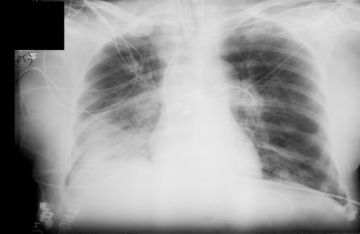

السوسنة - أفادت الدكتورة أوكسانا بلاتونوفا أخصائية الأشعة، أن الأشعة السينية لا تزال أداة تشخيصية مهمة، ولكن لا تزال المخاوف تحيط بها.

وتقول: 'الأشعة السينية هي إشعاع كهرومغناطيسي، مثل الأشعة فوق البنفسجية والضوء والحرارة. صحيح قد تلحق جرعاتها العالية الضرر بالخلايا، كالذي تسببه حروق الشمس. وأن الاستلقاء تحت أشعة الشمس على الشاطئ دون حماية أخطر بكثير من تصوير بالأشعة السينية للصدر مرة واحدة سنويا'.

وتؤكد بلاتونوفا، أن عدم اكتشاف المرض أخطر بكثير من الخضوع للأشعة السينية، حيث المعدات الحديثة تقلل من المخاطر، كما أن الفحوصات في الوقت المناسب تسمح بالكشف السريع عن الأمراض وبدء العلاج.